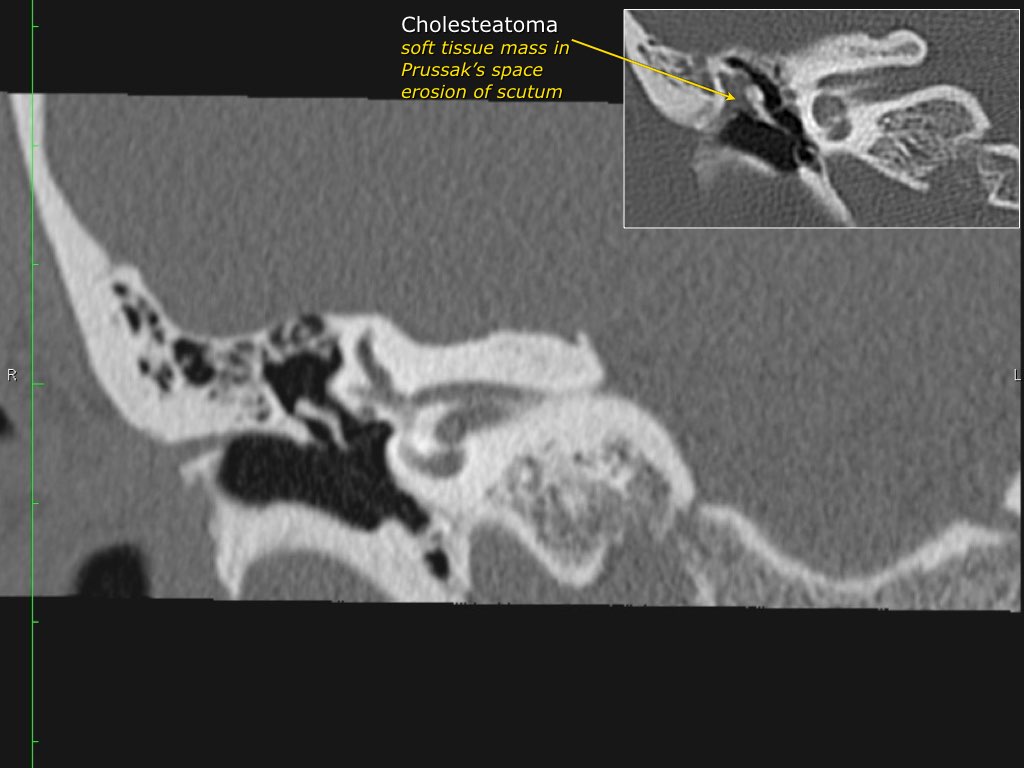

Pars flaccida là phần trên mỏng manh của màng nhĩ, liên quan đến rối loạn chức năng vòi nhĩ và cholesteatoma.

Hình ảnh một bệnh nhân có cholesteatoma.

Có một khối mô mềm ở vùng thượng nhĩ.

Scutum bị tù mòn.

Scutum

Đây thường là cấu trúc xương đầu tiên bị bào mòn do cholesteatoma, hình thành bởi sự co kéo vào trong của pars flaccida màng nhĩ vào vùng thượng nhĩ.